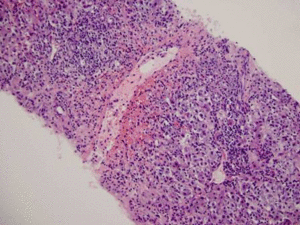

A Lump in the Neck M.C. Honigberg, et al.

This interactive case features a 44-year-old man with known HIV infection who presents with a large mass on the side of his neck. Test your diagnostic and therapeutic skills.